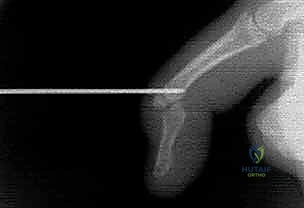

FIG 2 • A. Flexor digitorum profundus (FDP) avulsion in which a bony fragment has been caught up at the A4 pulley.

- FDP Avulsion (Jersey Finger): A lateral radiograph can reveal a bony fragment caught at the A4 pulley, indicating the level of tendon retraction.